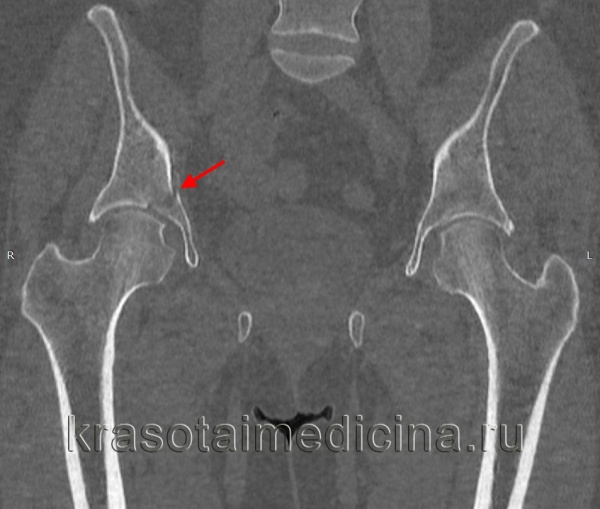

Рисунок 2. Рентгенограммы и МСКТ мужчины 39 лет. Автодорожная травма (удар в область левого вертела): вверху – при поступлении, комбинированный тип повреждения левой вертлужной впадины – неполный внутрисуставной перелом с поперечной линией излома, перелом задней стенки со смещением; внизу – после реконструкции и остеосинтеза поперечного перелома канюлированными винтами 7,3 мм, перелома задней стенки компрессирующими винтами 3,5 мм